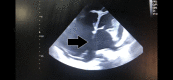

Figure 2. Large secundum atrial septal defect with a dilated right heart (black arrow)